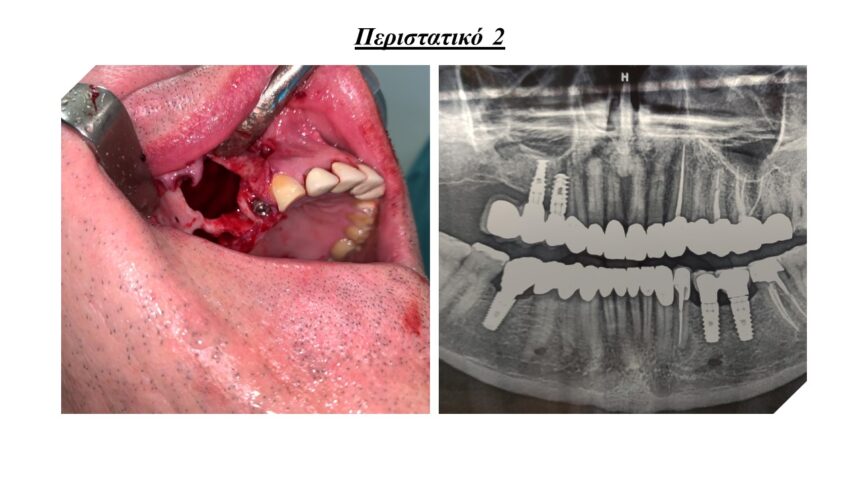

Άμεσα εμφυτεύματα και τεχνικές ώστε να αποφευχθεί η μακροχρόνια απορρόφηση της ακρολοφίας.

Τρισδιάστατη οστική ανάπλαση της ακρολοφίας με χρήση απορροφήσιμων , μη απορροφήσιμων μεμβρανών και μοσχευμάτων. Ενδείξεις, αντεδείξεις, πλεονεκτήματα - μειονεκτήματα.

Μεταξύ των επεμβάσεων - εφόσον υπάρχει χρόνος - θα παρουσιαστούν περιστατικά, ολοκληρωμένα από 20ετίας, τα οποία θα περιλαμβάνουν όλα τα παραπάνω ( τη χρήση μεμβρανών, PRF και ανύψωση της μεμβράνης ιγμορίου.